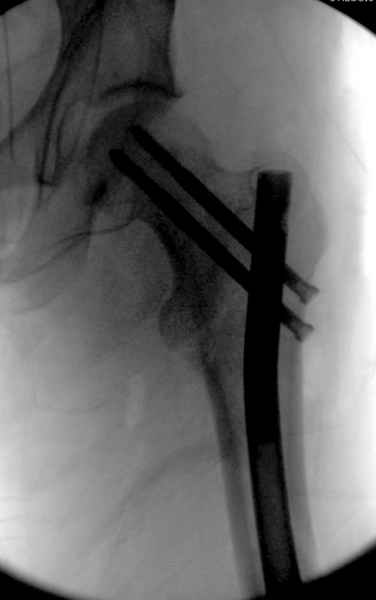

Второй случай тоже репозиция из малого доступа, больному 19 лет, множественные огнестрельные повреждениия конечностей, живота и черепа, правая конечность холодная, без пульсации. Ортопедический диагноз: огнестрельный перелом правого бедра. При срочной ангиографии повреждения сосудов не подтвердилось, конечность из-за ургентности состояния больного зафиксирована временным наружным фиксатором и больной оставлен на операционном столе для срочной лапаротомии хирургической службой.

Больной долго оставался нестабильным, только на 14 день удалось заменить на антеградный интромедуллярный штифт TFN (trochanteric femoral nail) SmithNephew. После неудачной попытки закрытой репозиции, несмотря на использование "joystick", проксимальный стержень от

наружного фиксатора, (перелом начал срастаться) репозицию провели из малого доступа, затем остальные этапы операции.

Случай был представлен из-за того, что больного оперировали после наружной фиксации и был риск инфекцирования через места проведения стержней (на снимках), прошло больше 3 месяцев, выписан из амбулаторной службы из-за отсутсвия надобности дальнейшего наблюдения.